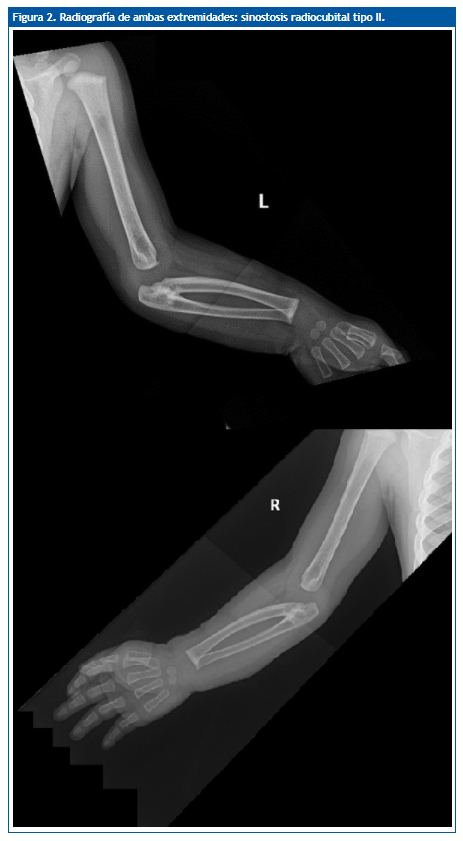

Se solicitó una radiografía de ambos brazos (Fig. 2) en la que se observó sinostosis radiocubital bilateral a nivel proximal, con ligera deformidad y subluxación de ambas cabezas femorales e incurvación diafisaria en los radios.

Figura 2. Radiografía de ambas extremidades: sinostosis radiocubital tipo II.

Nuestro caso correspondería a un tipo II. Clínicamente, son defectos que a veces pasan desapercibidos hasta los 3 o 4 años, cuando los padres o cuidadores observan cierto grado de dificultad para la supinación, como coger cubiertos, girar el pomo de las puertas, coger monedas o vestirse. El antebrazo se encuentra en pronación variable según la posición de la sinostosis. No conlleva una dificultad funcional importante, debido a que la persona, habitualmente, realiza movimientos compensadores con la articulación escapulohumeral, especialmente rotación externa y aducción, produciéndose, incluso, un aumento de los movimientos normales de esta articulación3. También suele existir hipermovilidad de la muñeca. En los casos bilaterales sin ningún grado de supinación, el grado de pronación es máximo y el paciente, en posición de firmes, tiene las palmas de las manos orientadas hacia atrás.